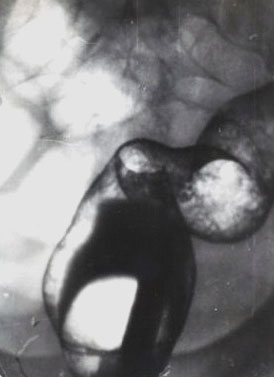

Неспецифический язвенный колит.

Рис. 2. Тот же больной. Поражение прямой и дистального отдела сигмовидной кишки с укорочением, выпрямлением контуров, характерным «зернистым» пневморельефом.